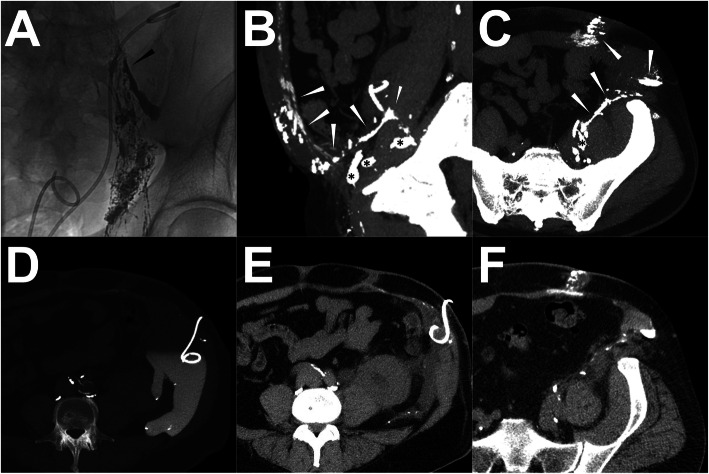

Fig. 6.

A patient underwent ALVE procedure after post-LAG CT. Note: Conventional iodized oil-based LAG showed the definite extravasation from three afferent LVs into the drainage (a). A similar demonstration was observed from the sagittal MIP images of post-LAG CT (b). The clear afferent LVs are shown (white arrowheads). The afferent LVs were punctured using the 21-G needles under the CT guidance penetrating the anterior and posterior walls (c). After the “cutting-off” embolization by using the histoacryl/lipiodol mixture (2:3) (d). The LF ceased immediately. Abbreviations: ALVE – afferent lymphatic vessel embolization; post-LAG CT – post-lymphangiographic computed tomography; LAG – lymphangiography; LVs – lymphatic vessels; LF – lymphatic fistula